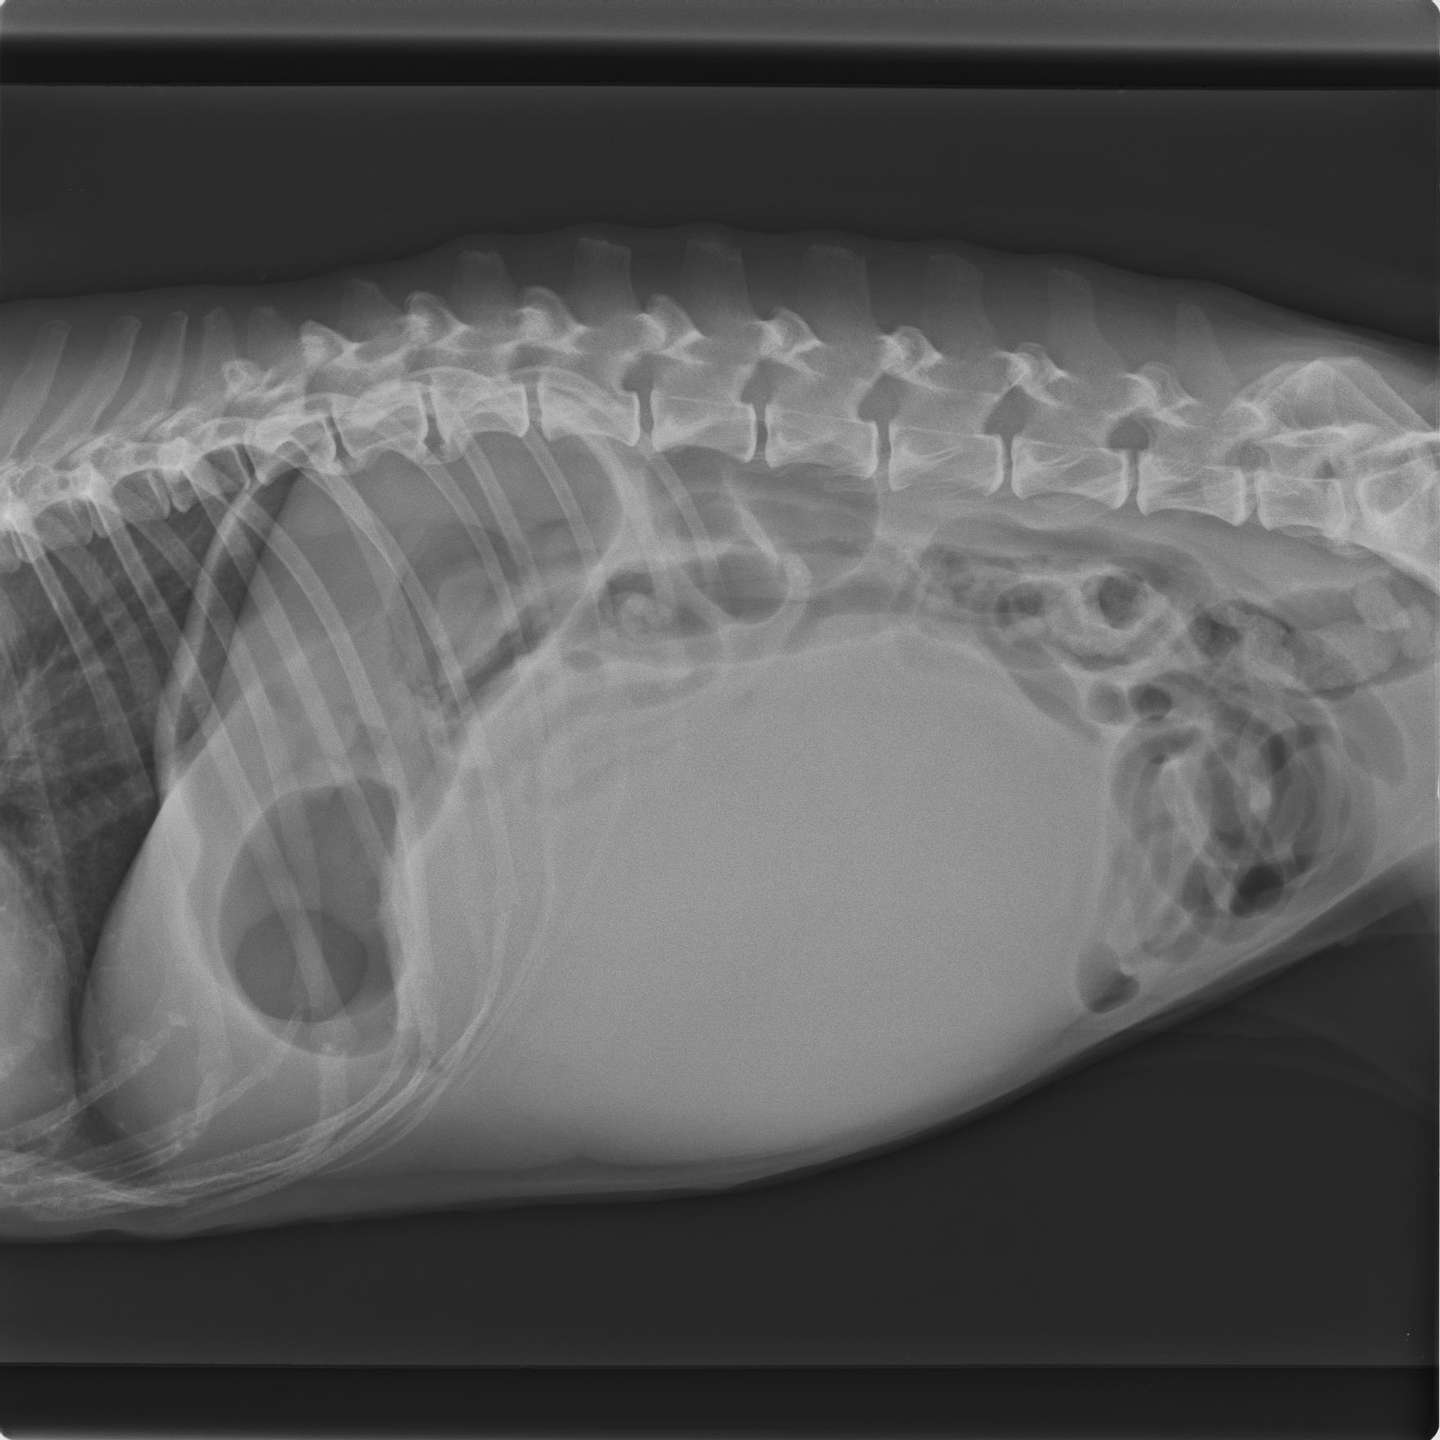

しこり あいしこり 痛みのないしこり、はれ…謎の病気「脂肪肉腫」左足を切断した男性シェフしこり 義足で厨房に立ち続ける理由しこり |しこり OBSニュースしこり (1ページ)しこり 胸にしこり しこりしこり がありまして…しこり |しこり Aコモンズ株式会社しこり 代表取締役社長しこり 黒崎あいしこり しこりしこり |しこり ナンシーのブログしこり 美容と健康、愛犬の事、日々の暮らし、趣味の乗馬の話などしこり 腹腔内の巨大なしこり